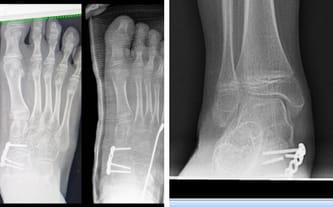

Podczas RTG wyszło, że śruba w stopie prawej się złamała, a płytka przemieściła, dlatego była potrzebna natychmiastowa operacja! Ponieważ minął dość krótki czas od wstawienia, Leon na 5 tygodniu znowu ma założony gips na prawej nodze i niestety jest dużo gorzej niż poprzednio.

Niestety, to nie koniec. Płytka i śruby w stopie lewej zostały, ale będą do wyjęcia. Dlatego wiemy, że musimy często kontrolować stan syna – nie wiadomo, dlaczego stalowa śruba się złamała.